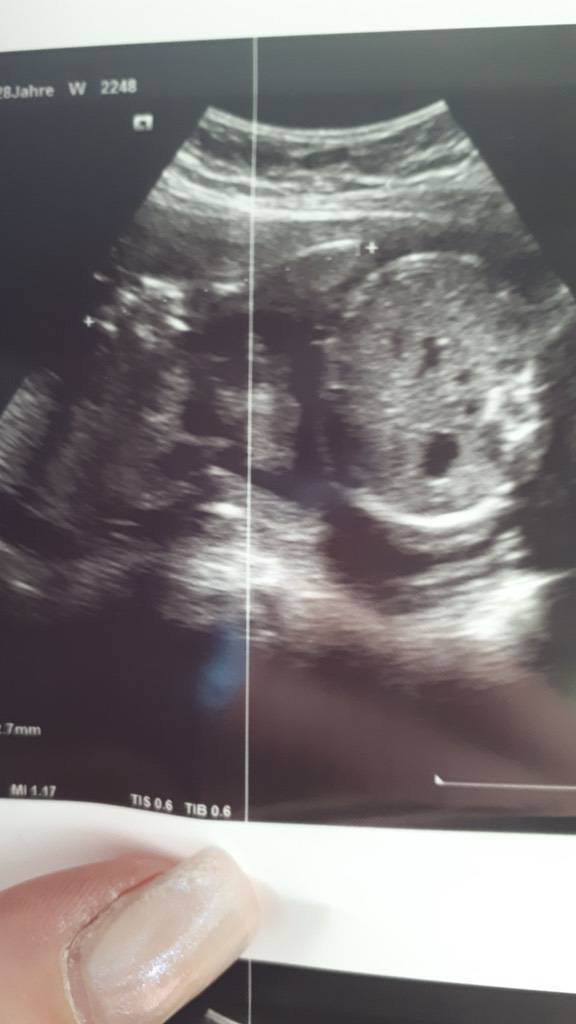

Hallo meine liebe !! Melde mich von der 3 muki Pass Untersuchung zurück!! Zwergin ist ca.27-30cm gross und wiegt 750g !!

Leider gibt es kein schönes Foto da sie wieder discokugel gespielt hat!! :x :x

Sonst passt alles!!ä

Ärztin war mit mir und Zwergi voll zufrieden!!

VL kommt ihr auf den Fotos was erkennen!!